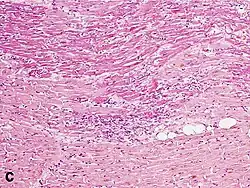

Under the microscope, myocardial infarction presents as a circumscribed area of ischemic, coagulative necrosis (cell death). On gross examination, the infarct is not identifiable within the first 12 hours.[22]

Although earlier changes can be discerned using electron microscopy, one of the earliest changes under a normal microscope are so-called wavy fibers.[23] Subsequently, the myocyte cytoplasm becomes more eosinophilic (pink) and the cells lose their transversal striations, with typical changes and eventually loss of the cell nucleus.[24] The interstitium at the margin of the infarcted area is initially infiltrated with neutrophils, then with lymphocytes and macrophages, who phagocytose ("eat") the myocyte debris. The necrotic area is surrounded and progressively invaded by granulation tissue, which will replace the infarct with a fibrous (collagenous) scar (which are typical steps in wound healing). The interstitial space (the space between cells outside of blood vessels) may be infiltrated with red blood cells.[22]

These features can be recognized in cases where the perfusion was not restored; reperfused infarcts can have other hallmarks, such as contraction band necrosis.[25]